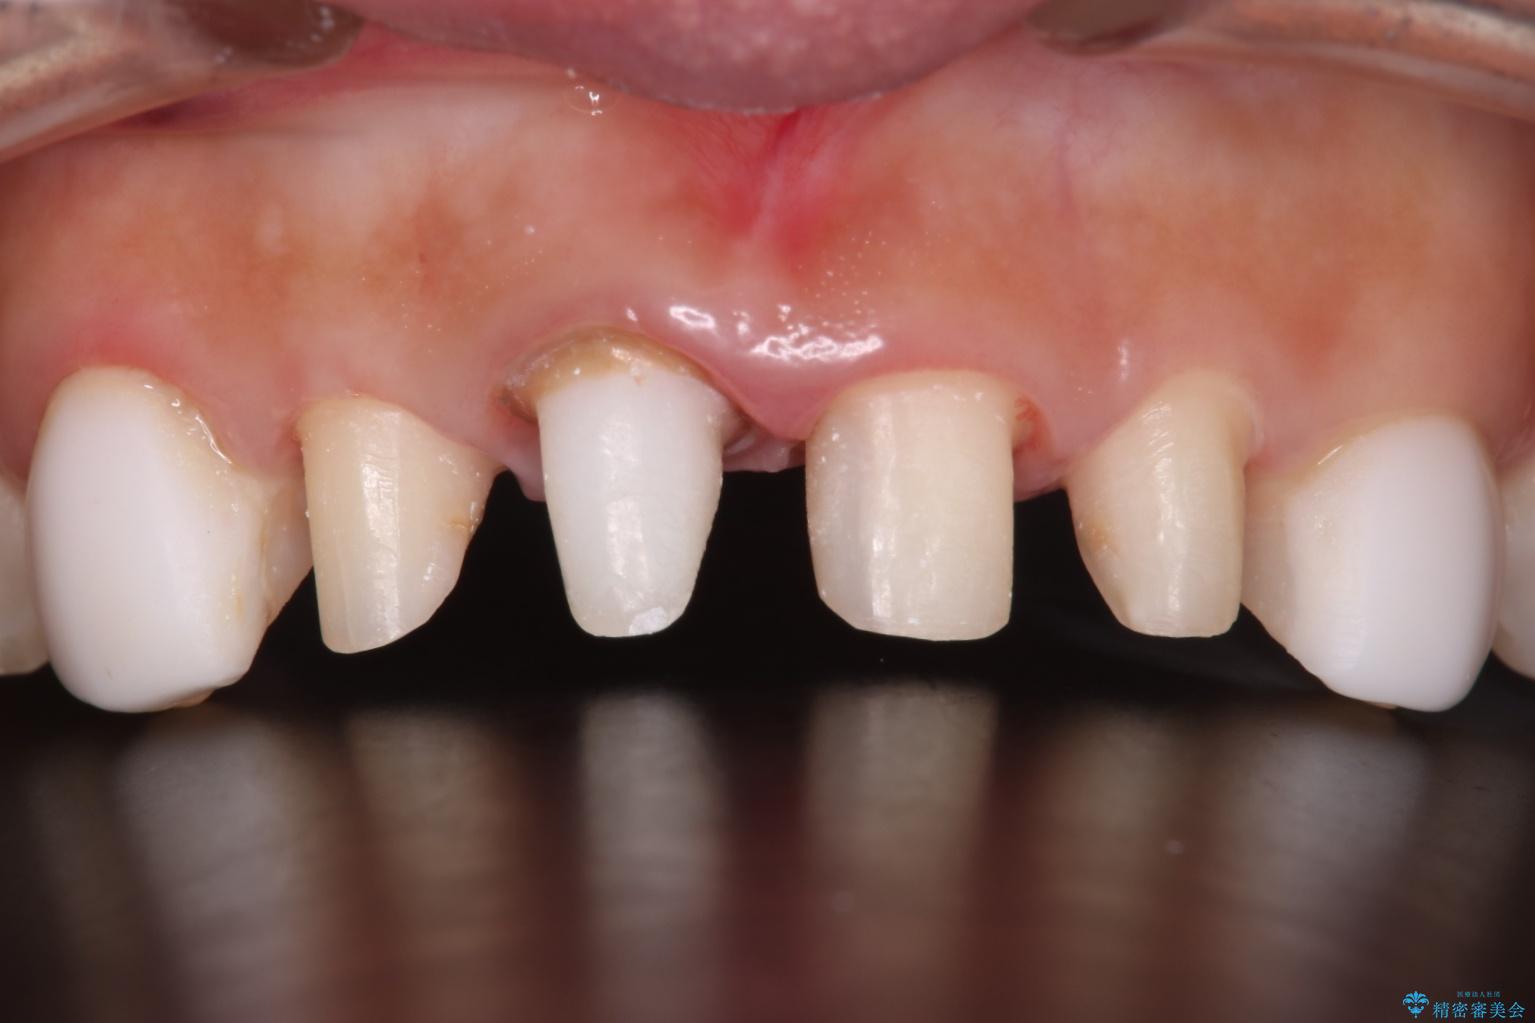

- 他院で治療した前歯の色が気になるということで来院された患者様です。前歯に色の差があり、レントゲンから内部にう蝕も見られたため、審美性に優れ、う蝕になりにくいオールセラミッククラウンで治療いたしました。

清掃性も上がったおかげで、歯肉の状態も良好に保てています。

色の調和もとれたので非常に満足いただけました。